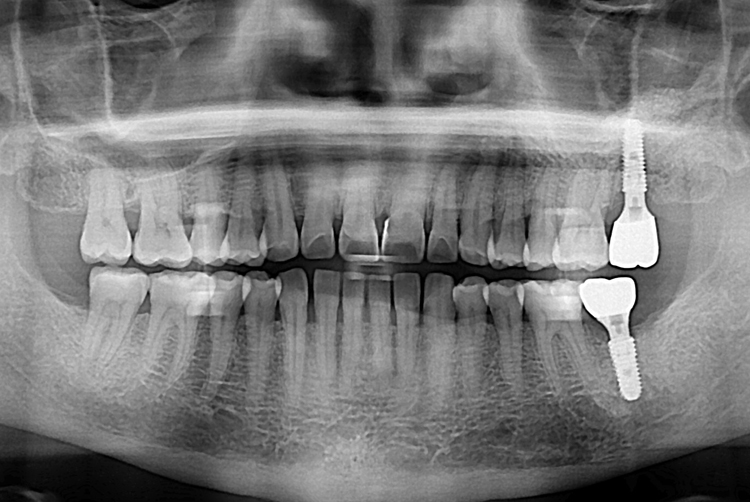

[임플란트] 어금니 임플란트

치료후 : 2018-01-24

세종치과는 많은 환자와 다양한 케이스를 바탕으로

항상 편안한 임플란트 수술을 제공하고자 노력하고,

오래동안 튼튼히 쓸 수 있는 임플란트 수술을 가장 큰 목표로 삼고 있습니다.